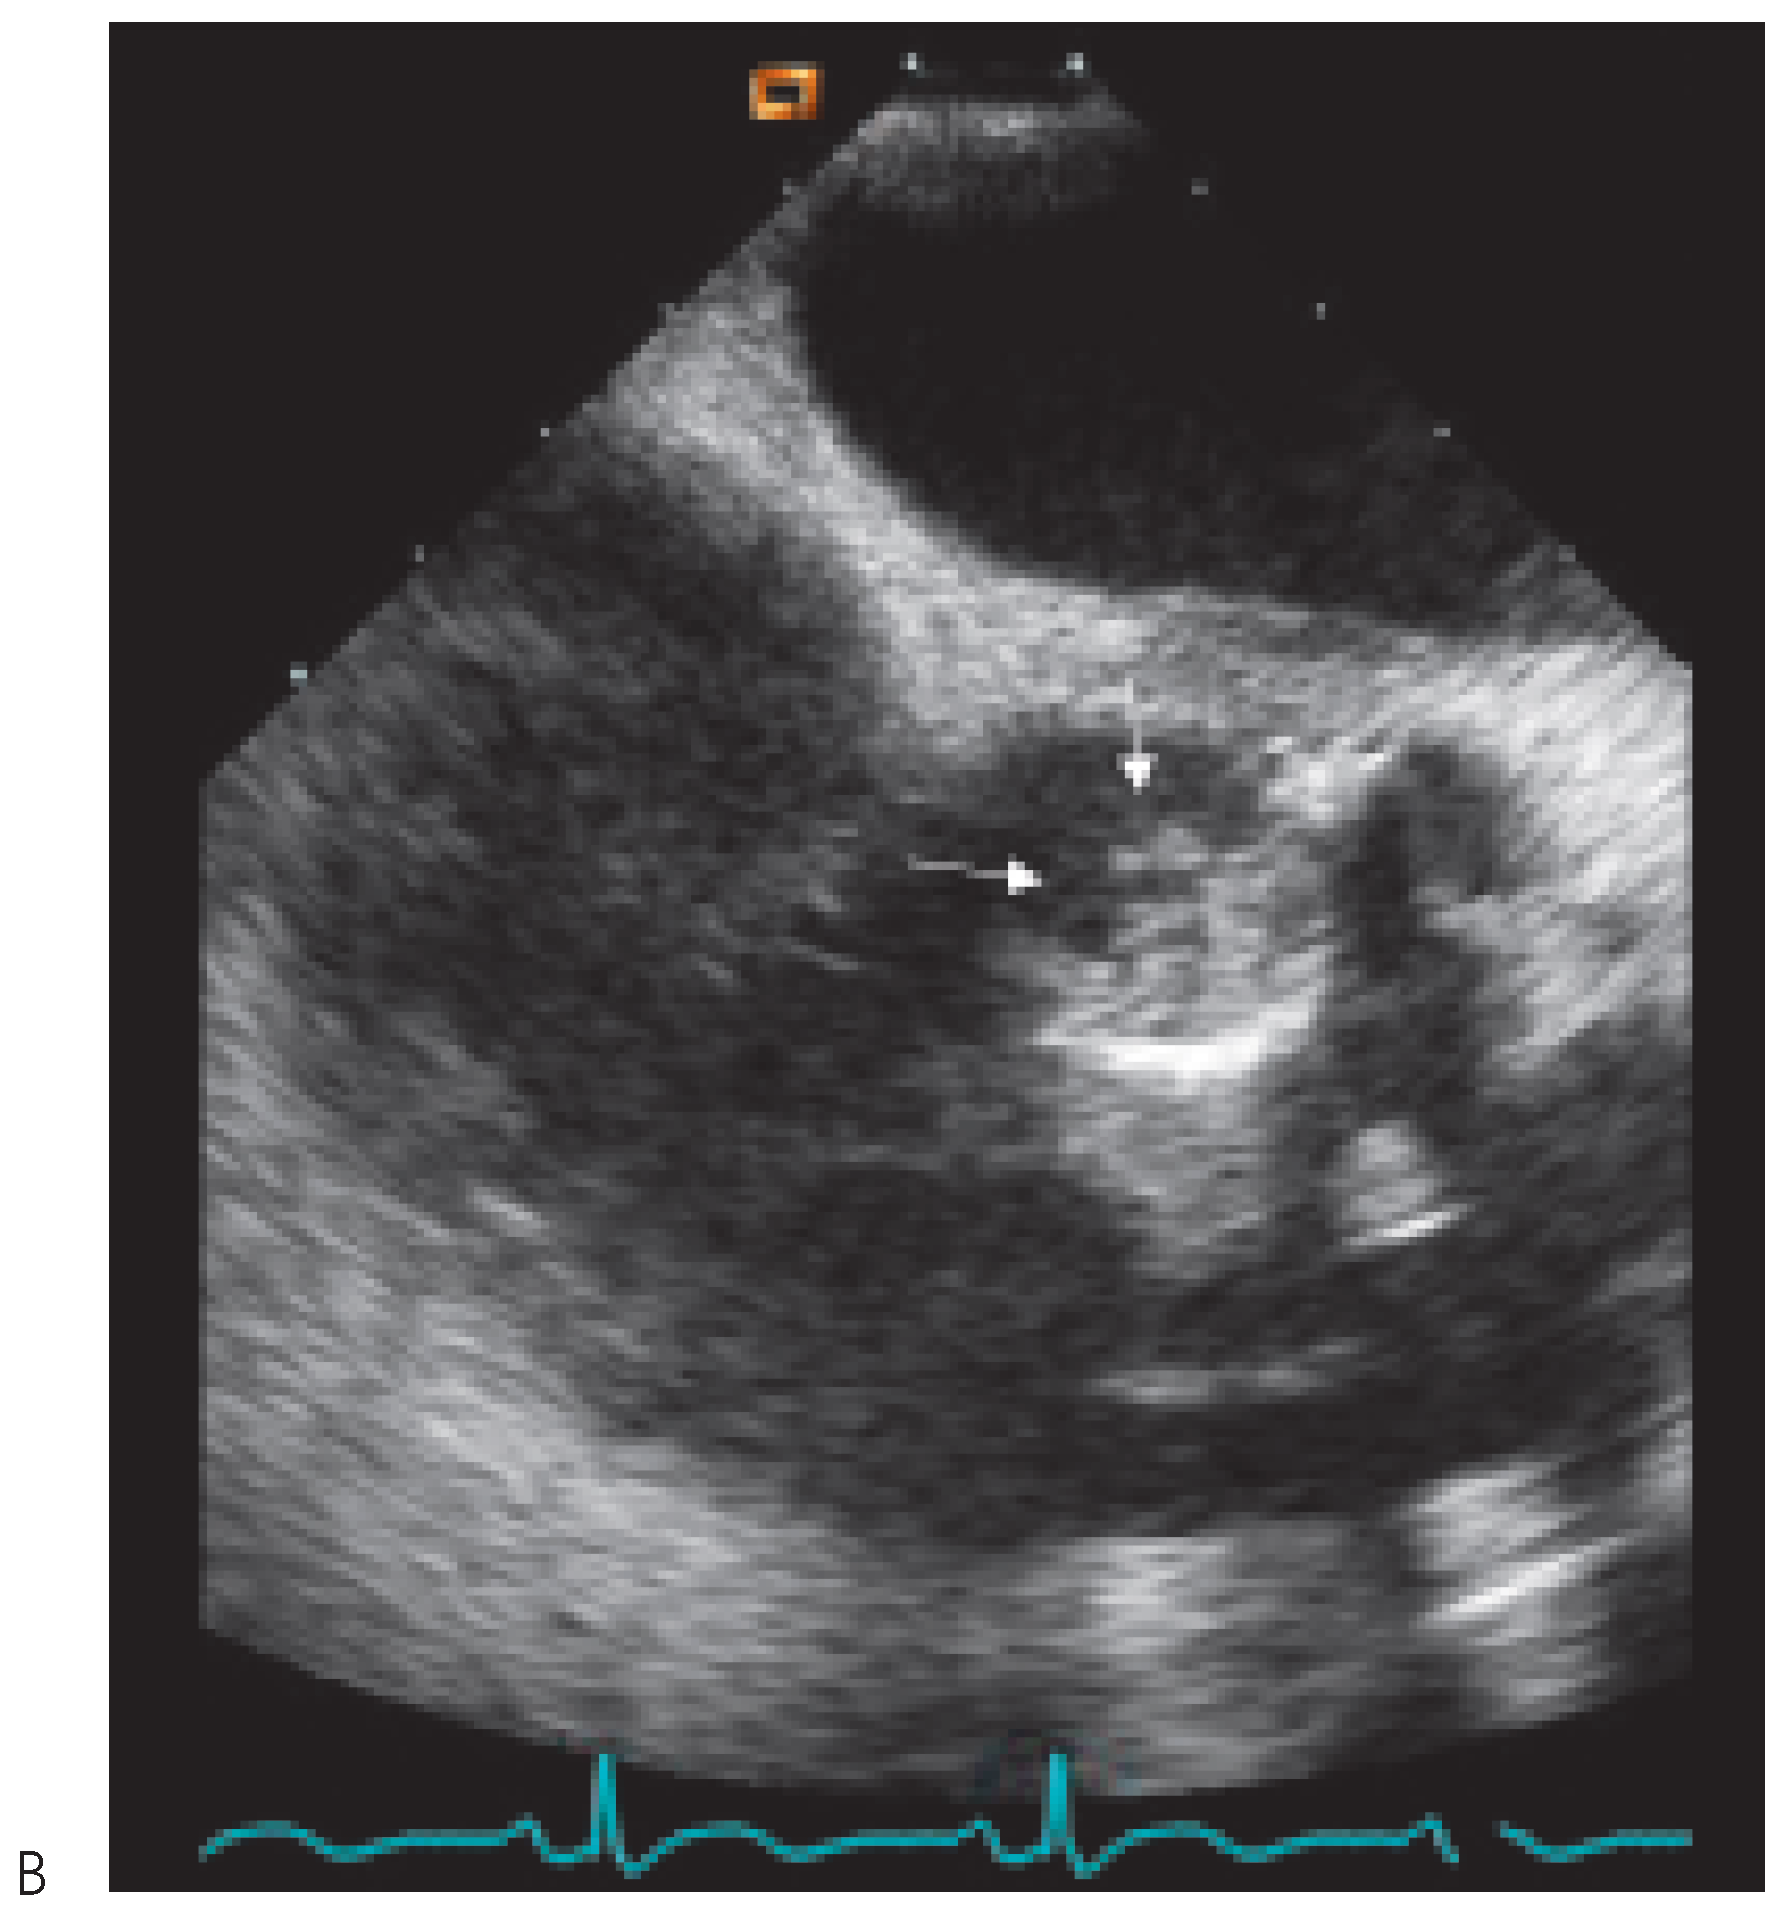

Transthoracic echocardiography was performed with only apical views available (Figure 1). It demonstrated abnormal motion of the prosthesis annulus but only a mild aortic insufficiency. Neither vegetations nor abscess were visualised. As the probability of prosthetic endocarditis was high, a transoesophageal echocardiography (Figure 2 and Figure 3) was organised immediately afterwards. It demonstrated a partially dehiscent prosthesis due to a subjacent hemicircumferential paraprosthetic abscess. This abscess has spontaneously drained, leaving a large cavity. Large vegetations were also observed on the leaflets of the bioprosthetic valve.

Figure 2. TEE apical 3 cavity view. The dehiscence (big arrow) is well visualised located in the anterior part of the annulus. Vegetations are also seen (small arrow) on the bioprosthetic leaflet.